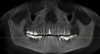

Снимок:

Вопрос о мосте 5-8. двух зубов нет уже около 30 лет. Имплантация возможна только после костной пластики, операция достаточно сложная, выполняется под общим наркозом, успех не гарантирован(если не так поправьте) поэтому хотелось бы обойтись без нее. Есть ли возможность заменить имеющийся железный мост новым? Желательно сохранить зубы живыми, не обтачивать сильнее чем есть. Диоксид циркония дает такую возможность?

P.S. Верхние 6, 7, 8 планируется удаление и имплантация.